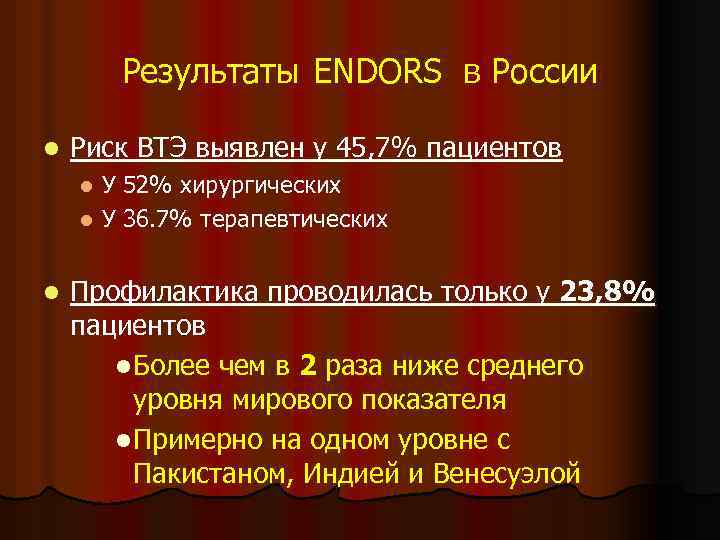

Результаты ENDORS в России l Риск ВТЭ выявлен у 45, 7% пациентов У 52% хирургических l У 36. 7% терапевтических l l Профилактика проводилась только у 23, 8% пациентов l Более чем в 2 раза ниже среднего уровня мирового показателя l Примерно на одном уровне с Пакистаном, Индией и Венесуэлой